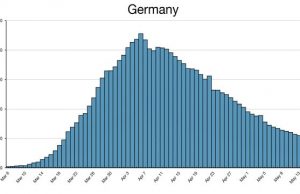

Time to rethink predicting pandemic infection rates?

During the first months of the COVID-19 pandemic, Joseph Lee McCauley, a physics professor at the University of Houston, was watching the daily data...